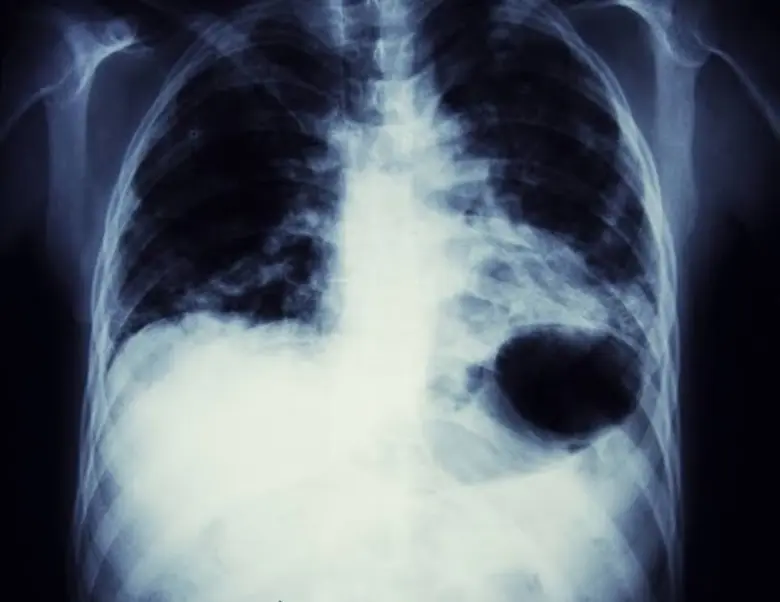

เกี่ยวกับ NSCLC

ในช่วงไม่กี่ปีที่ผ่านมา จีนมีอุบัติการณ์มะเร็งปอดเพิ่มขึ้น จากการประมาณการล่าสุดเกี่ยวกับภาระมะเร็งทั่วโลกโดย International Agency for Research on Cancer (IARC) พบว่าในปี 2563 จีนมีผู้ป่วยมะเร็งปอดรายใหม่ประมาณ 0.82 ล้านราย และผู้เสียชีวิตจากมะเร็งปอด 0.71 ล้านราย ทั้งนี้ มะเร็งปอดเป็นสาเหตุอันดับหนึ่งของการเสียชีวิตที่เกี่ยวข้องกับมะเร็งในประเทศจีน และ NSCLC เป็นมะเร็งปอดชนิดที่พบบ่อยที่สุด

ปัจจุบันยังมีตัวเลือกการรักษาที่จำกัดสำหรับผู้ป่วยโรคมะเร็งปอดชนิด NSCLC ระยะลุกลามเฉพาะที่/หลายตำแหน่ง (ระยะที่ III) และระยะแพร่กระจาย (ระยะที่ IV) โดยในประเทศจีนนั้น การให้ยาเคมีบำบัดตามด้วยการฉายรังสีเป็นวิธีการรักษาที่ใช้กันอย่างแพร่หลาย ในขณะที่การให้ยาเคมีบำบัดร่วมกับการฉายรังสีนั้นยังอยู่ในวงจำกัด อย่างไรก็ตาม การรักษาทั้งสองแบบให้ผลที่ไม่น่าพอใจ